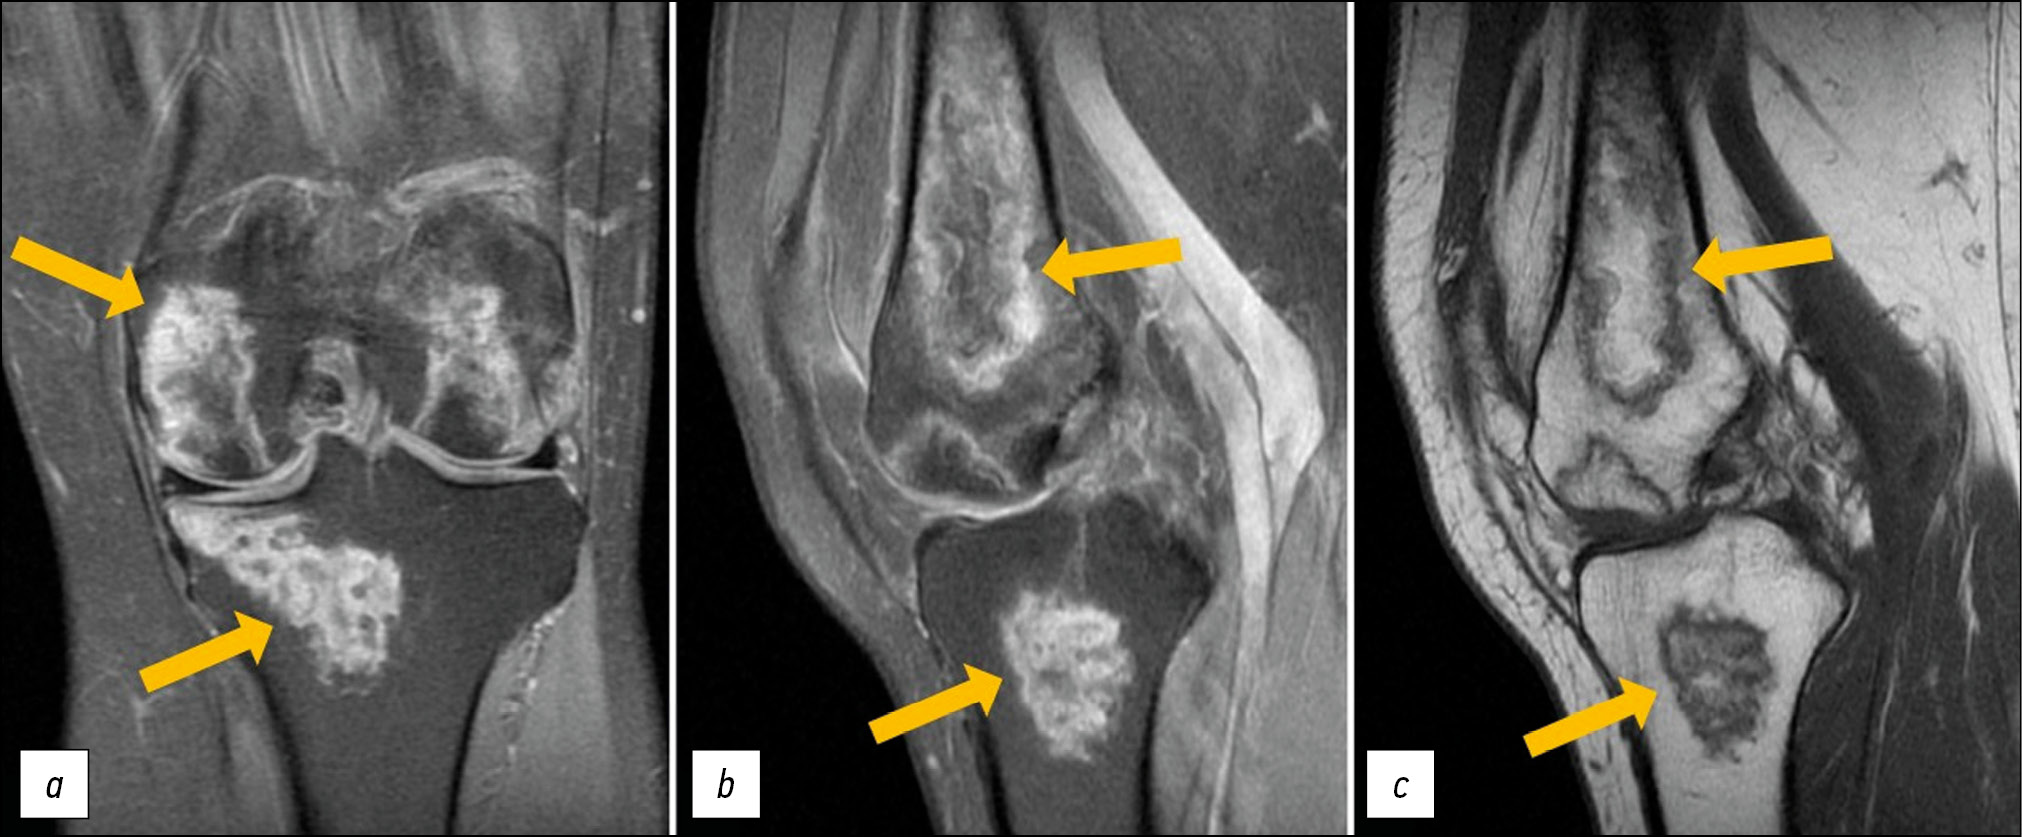

MRI of the left knee joint: lesions in the distal parts of the femoral diaphysis and femoral condyles (with involvement of the articular surface) as well as in the patella, inhomogeneously hyperintense on PD-weighted (proton-weighted) images with fat suppression and hypo-/isointense on T1-weighted images (T1WI), with an irregular (“geographic”) shape and yellow marrow signal areas visualized in the central parts (Fig. 1). MRI of the right knee joint: similar lesions of the bone marrow of both femoral condyles, with involvement of the distal metaepiphysis and articular surface of the lateral condyle as well as the patella. A perilesional “double line” sign is visualized over a short distance for some lesions (Fig. 2).

Fig. 2. Primary MRI of the right knee joint: PDWI with fat suppression in the coronal (а) and sagittal (b) plane and T1WI in the sagittal plane (с). Thick arrows indicate areas of bone marrow edema in the form of a heterogeneous, irregularly shaped (“geographic”) MRI signal of femoral condyles and patella; thin arrows indicate the “double line” sign in the form of internal hyperintense (granulation tissue) and external hypointense (osteosclerosis) lines on PDWI.